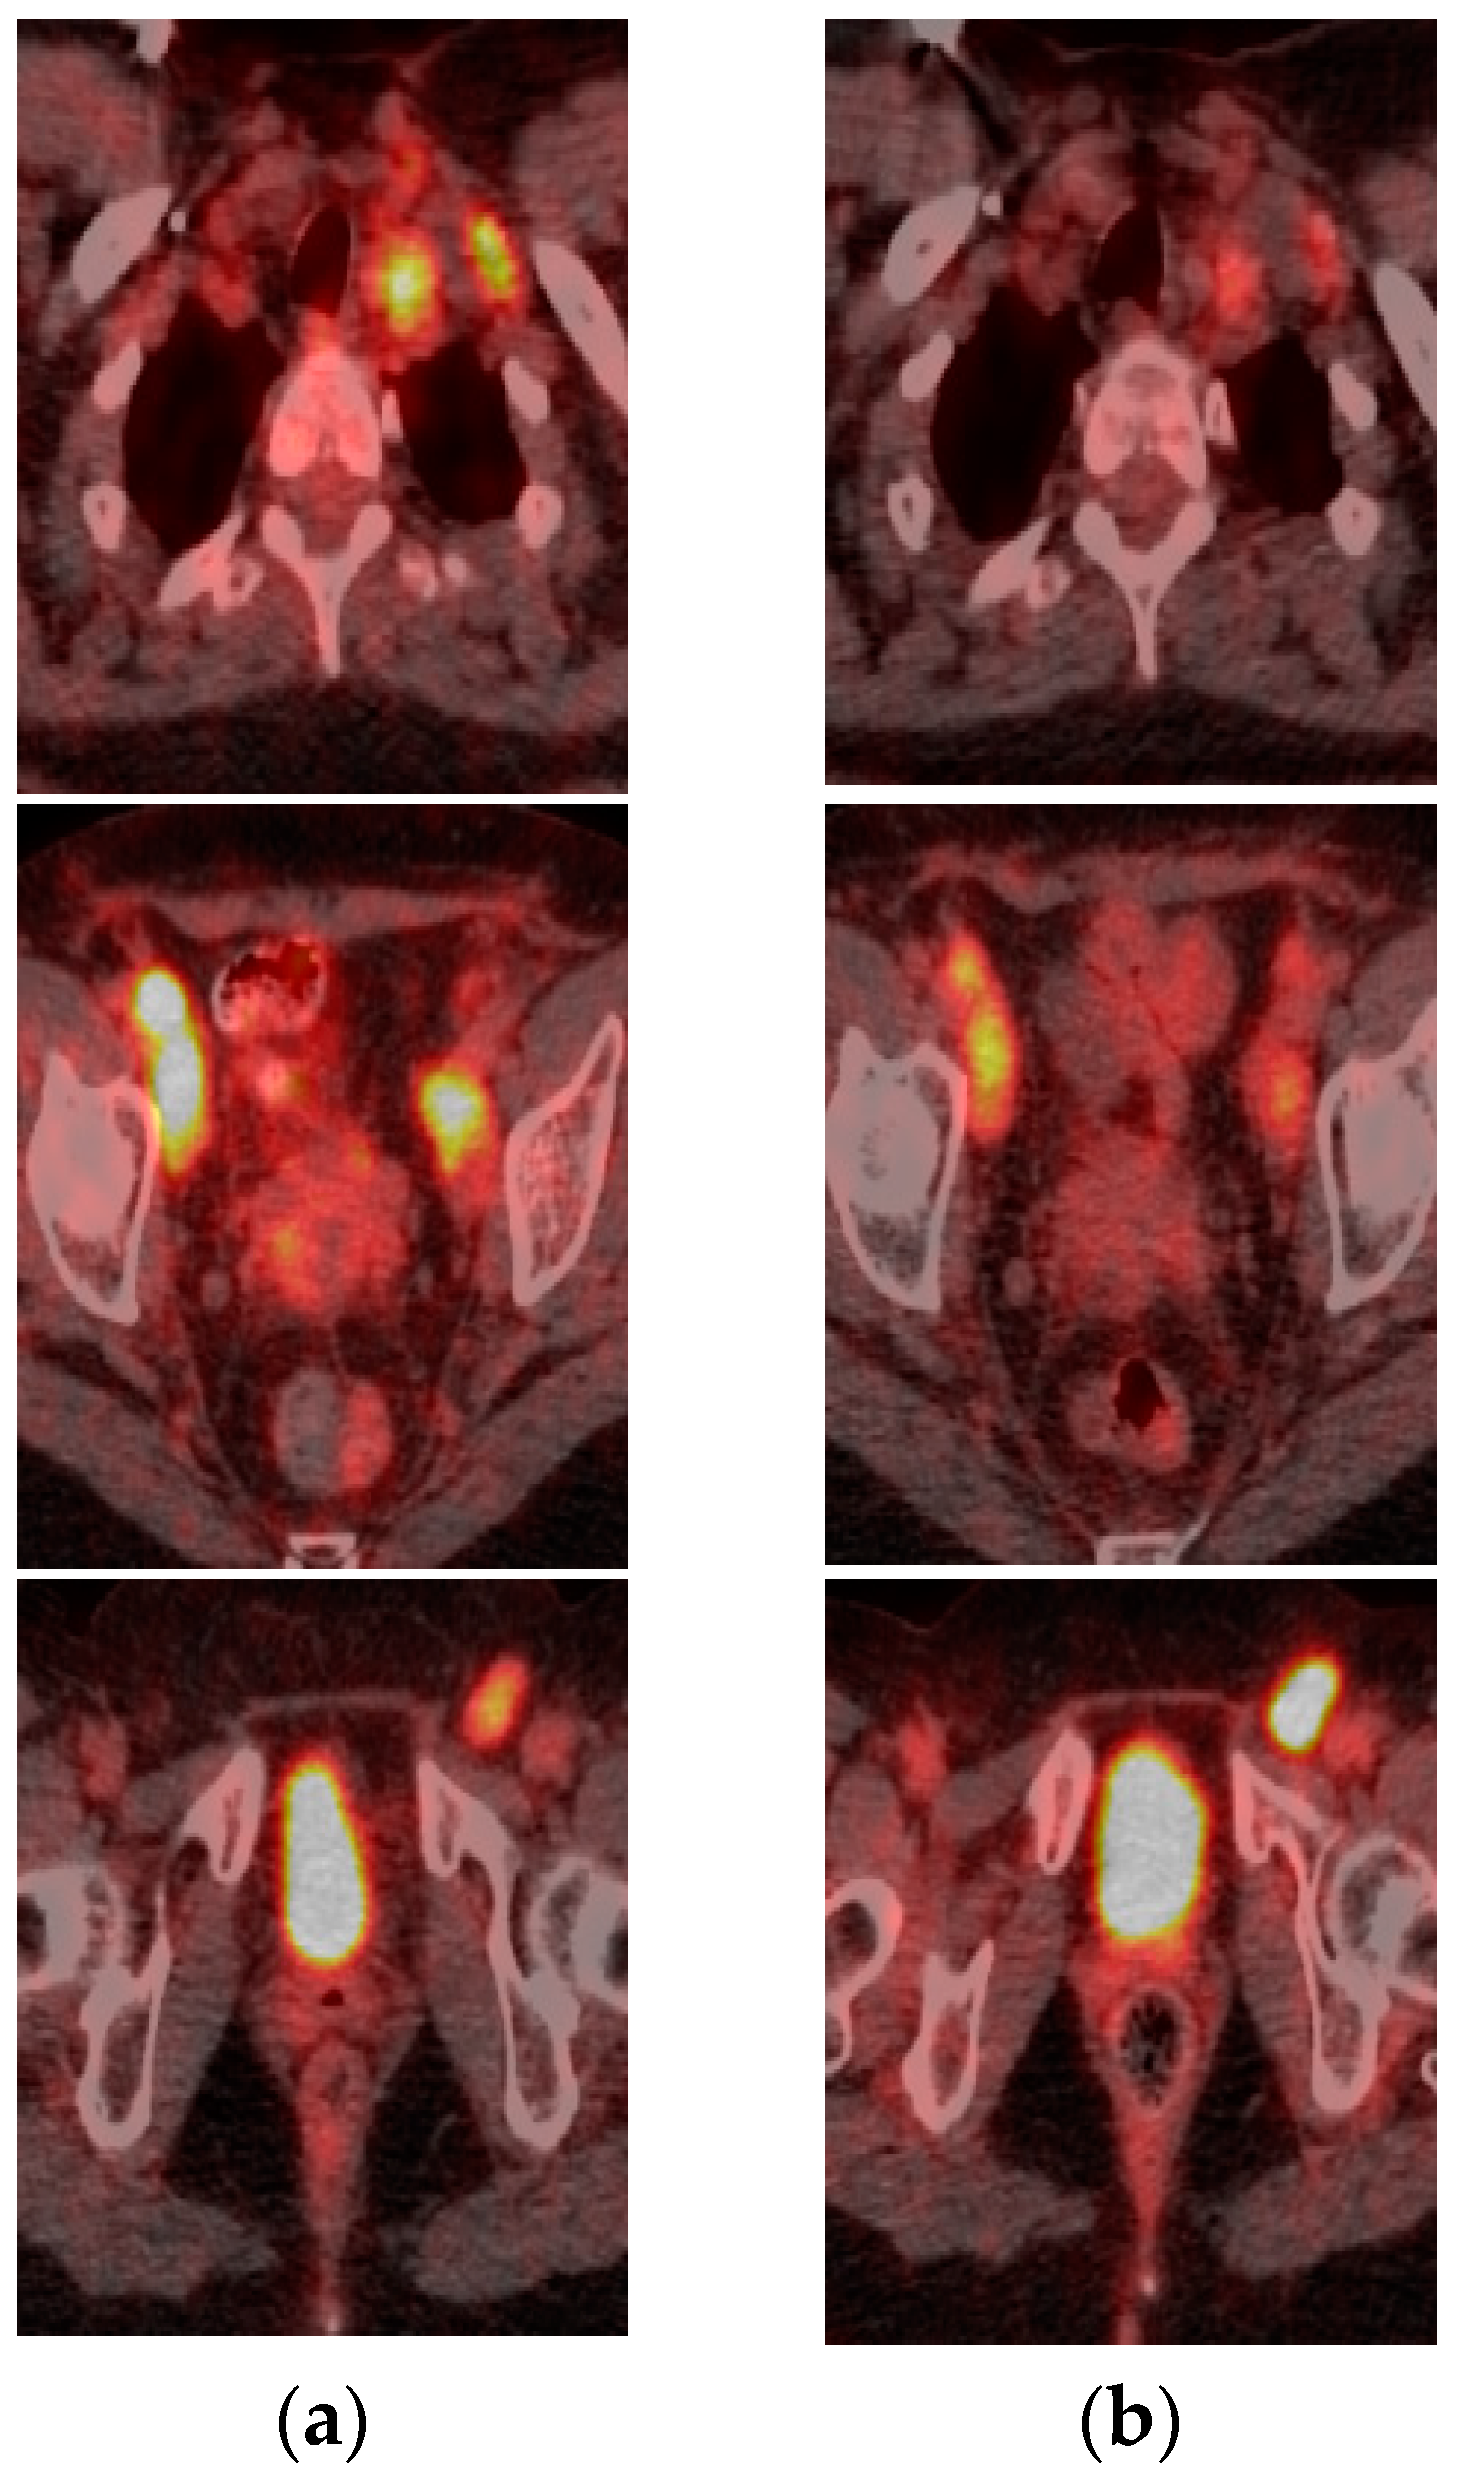

2.1. Case 1

2.2. Case 2